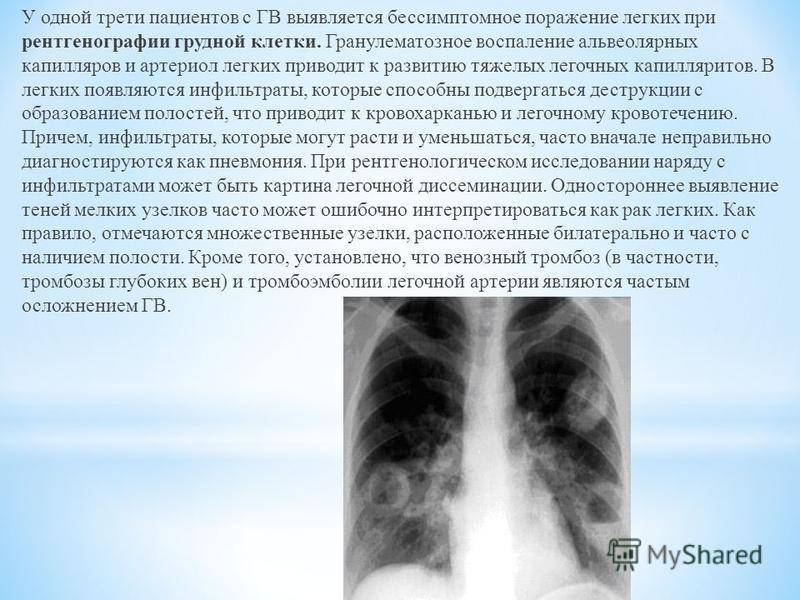

Фотографии, демонстрирующие обнаруженное усиление легочного рисунка

Раздел: Фотодневник открытий